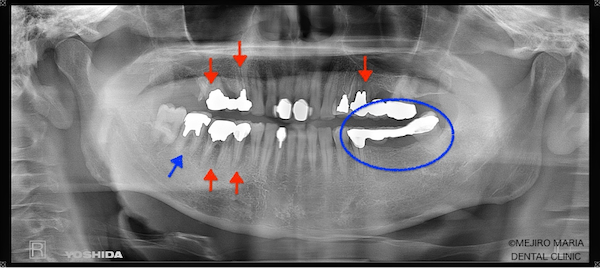

患者様は、長年にわたり臼歯部(奥歯)の噛み合わせの調子が悪いことと、食事の際に痛みを感じることを主訴に来院されました。前歯部から口腔内を確認すると大きなトラブルは確認できませんが、レントゲン撮影と口腔内診査を行うと、多数の臼歯部の歯牙(歯)が歯根破折により抜歯を余儀なくされる状況でした。

まずは、歯周組織検査を含めた口腔内診査、レントゲン写真の撮影により、保存できる歯牙と、抜歯をせざるを得ない歯牙などを選定しました。

今回の症例では、歯根破折していた5本の歯牙(下の写真・赤矢印)に対して、抜歯を提案した。また、診断用WaxUp(ワックスアップ)を行ったところ左下のブリッジ(青丸)と右下(青矢印)の噛み合わせ平面が乱れており、咬合に負担をかけていることが予想されました。そのため、最終的にそれらの不調和を改善し、適切な噛み合わせにすることをゴールとして治療を開始しました。